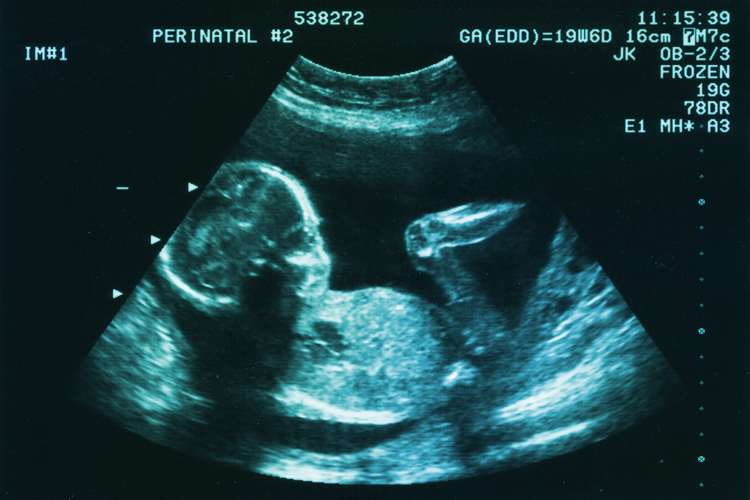

Can children-in-utero feel pain?

20_weeks (1)The Pain Capable Act (HR 1797, “Pain Capable Unborn Child Protection Act”), effectively banning abortion after 20 weeks, just passed the house this May (2015) and is set to go before the Senate. As of today it’s being reviewed in a judiciary committee. If it passes the Senate, it will likely be vetoed by President Obama. If children-in-utero do feel pain, then most (perhaps all) senate democrats and the President consider that a worthwhile cost in protecting late-term abortion as a right (20+ weeks).

There are some roadblocks to this legislation however, not the least of these being the abstract nature of “pain.” Children in utero allegedly feel pain as early as 8 weeks gestation and at least by week 20. “Alleged” is the proper term here because the nature of pain is private, and there are some problems with quantifying pain as an object for legal analysis. One cannot extract pain, measure it out in a beaker, and divide it into parts. It’s not a public object like that. It’s deeply private, being a subjective state of experience. There’s no amount of scientific analysis that can ever bridge the medical doctor or the lab technician into another person’s felt experience of pain.

As it turns out, children-in-utero do have the material and active features corresponding to pain reception.

Many more medical professionals could be cited in support of this growing concensus. That is, children-in-utero have the neurology to receive pain signals through a comprehensive neural system linking to the thalamus (where pain reception occurs) as well as respond to those signals through their endocrinology  (hormonal release) and muscular systems (responding to environment, avoiding injury). All of these are present at least by the 20th week of development.

Specifically, children-in-utero are known to avoid forcepts, resist poking and prodding, squirm under the knife, and in the case of fetal surgery they have to be anaesthetized because they move as if they felt pain. Indeed fetal surgeons are required to administer anesthesia for fetuses 18 wks or older.